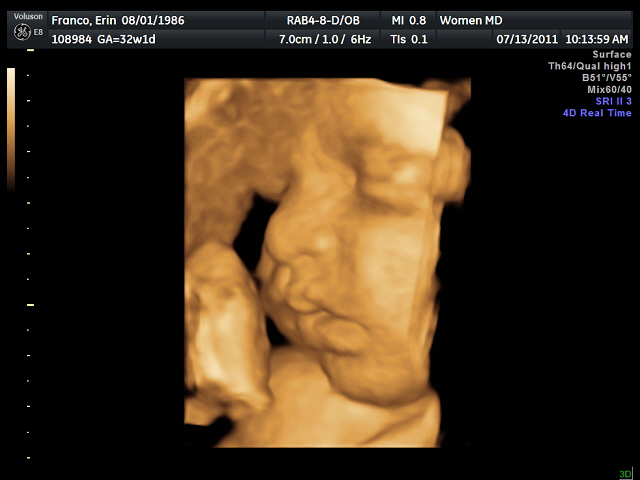

We had our 32-week ultrasound this morning, and we got some gorgeous pictures of our baby girl! We are due Sept. 6. I can’t wait to meet this little one…

At around 4lb, so far she is in a healthy 38th percentile range for weight. Both she and I are doing great as we move into the home stretch of the pregnancy.

Sweet Baby girl!